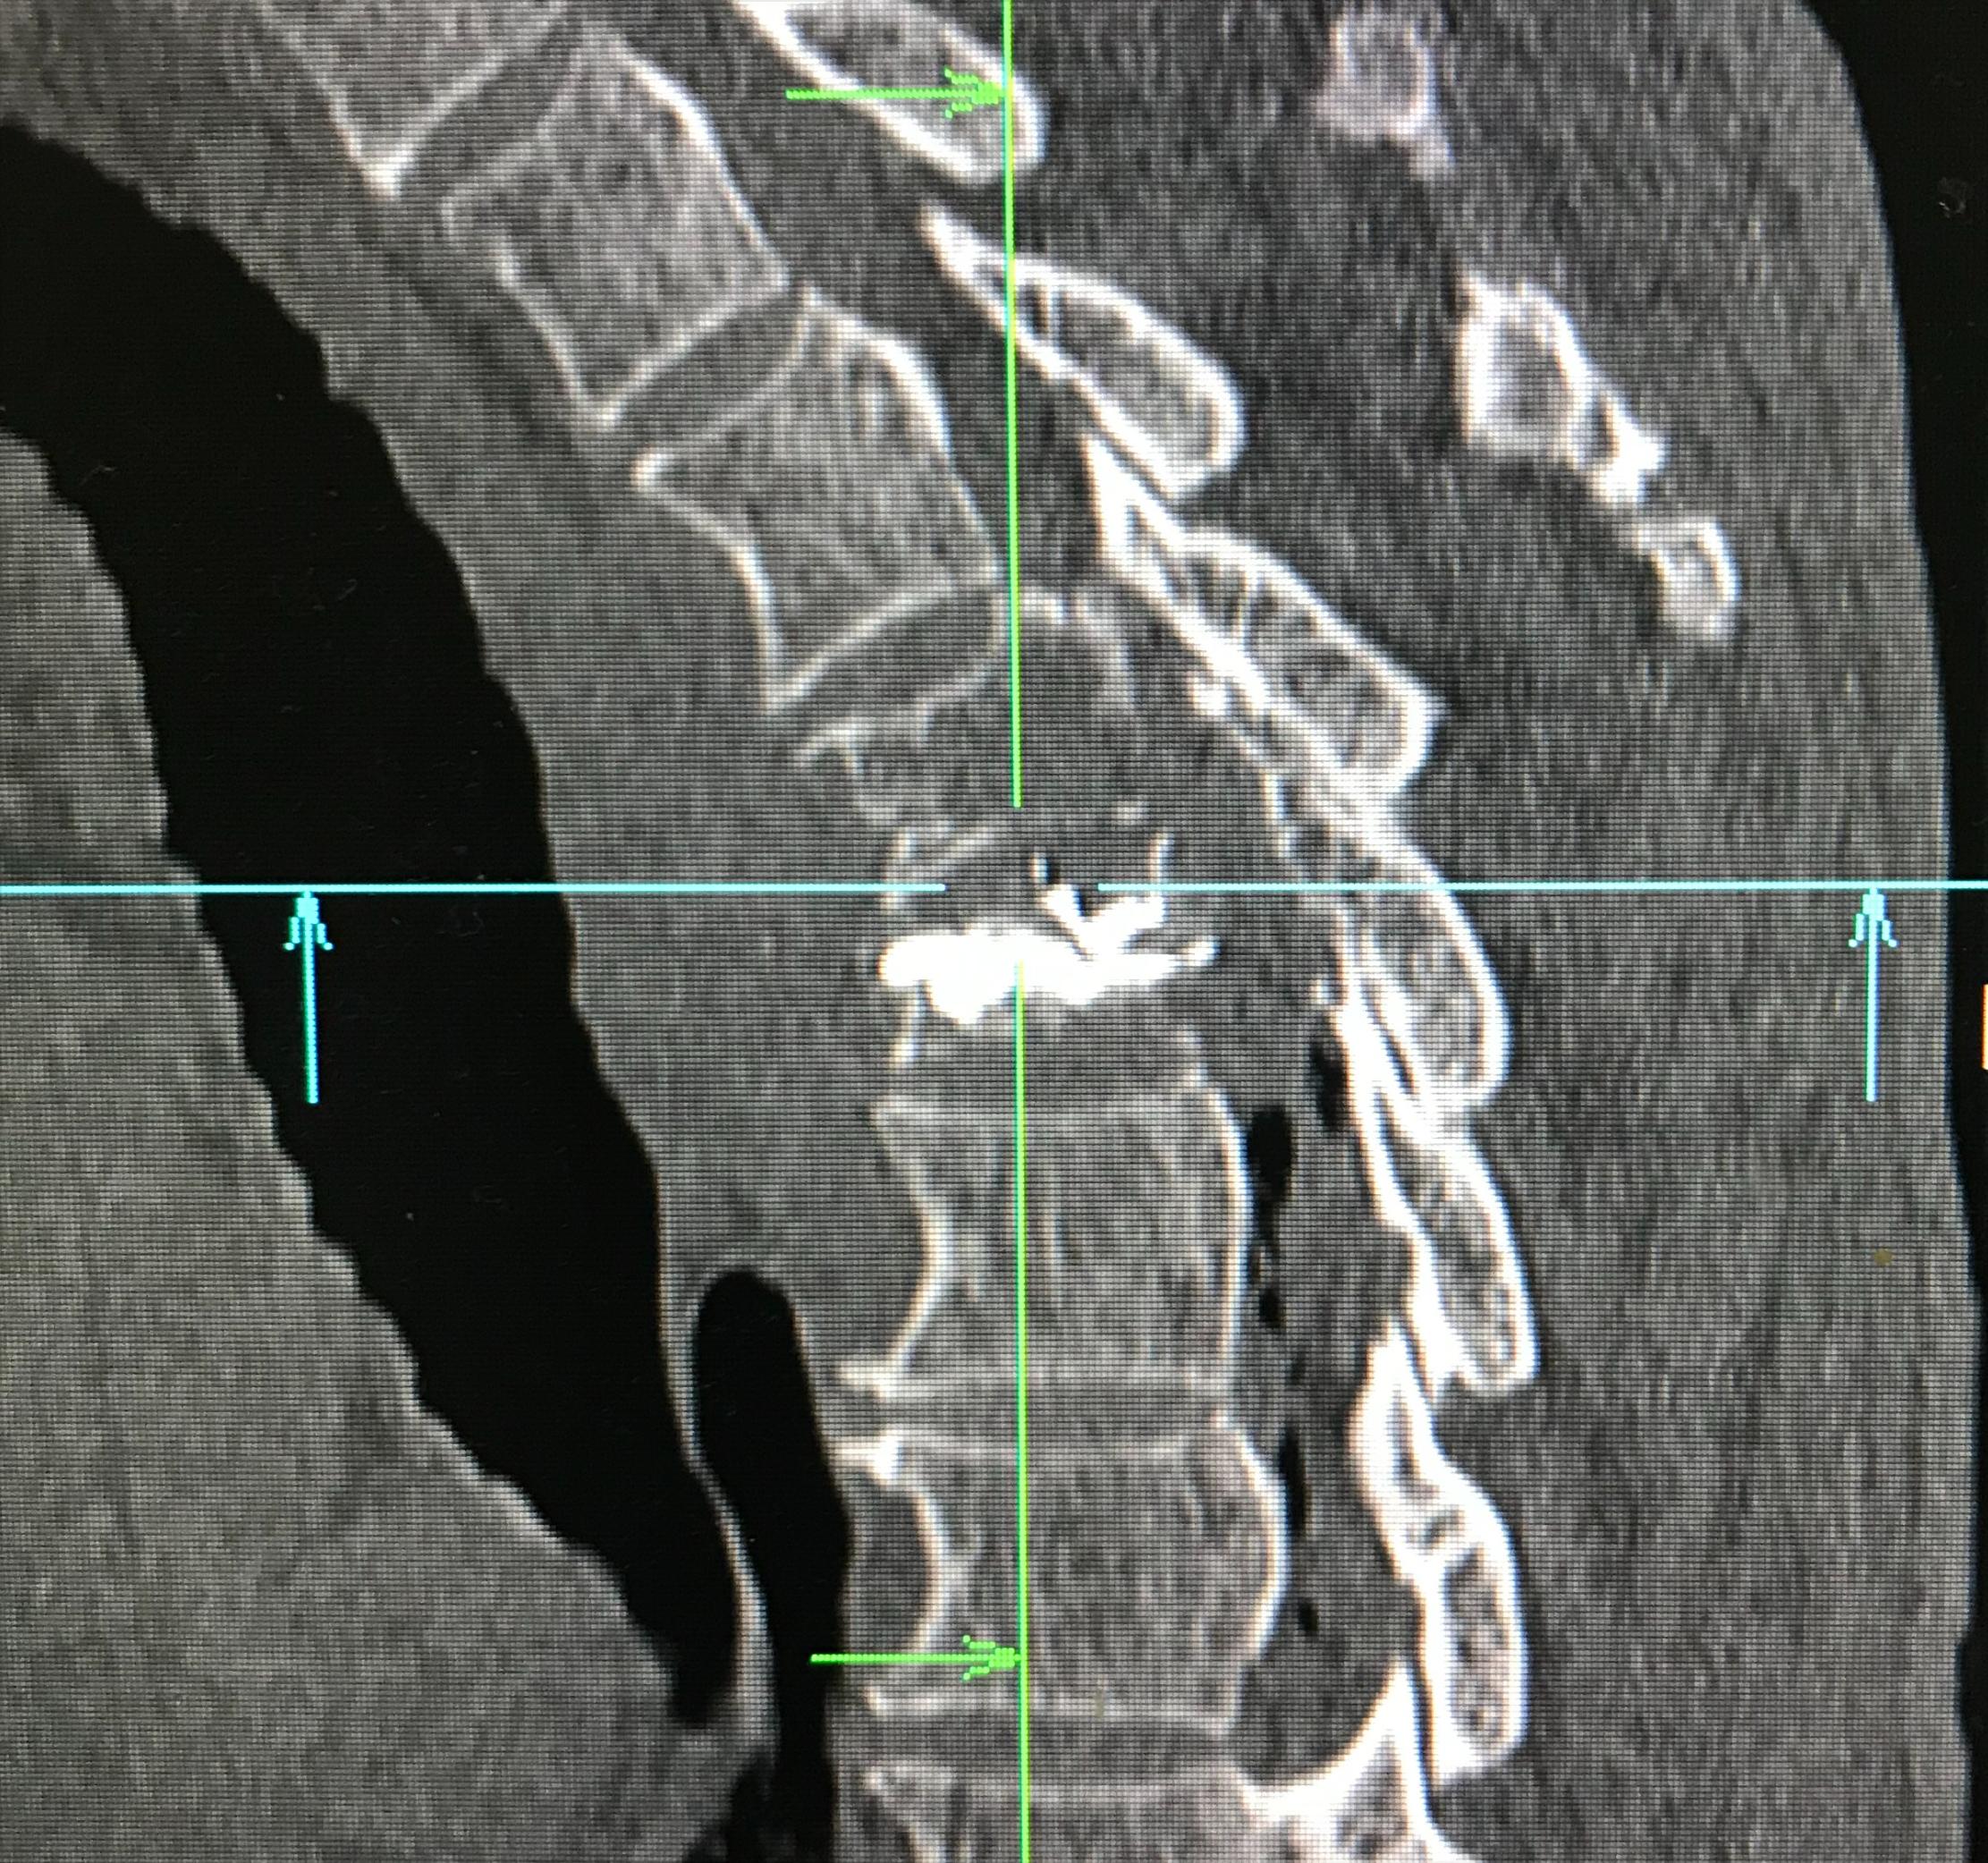

经皮椎体成形术术后进行CT扫描,重建后显示骨水泥在T5椎体内充填到位,且分布良好。

PVP术后矢状位重建示骨水泥分布良好